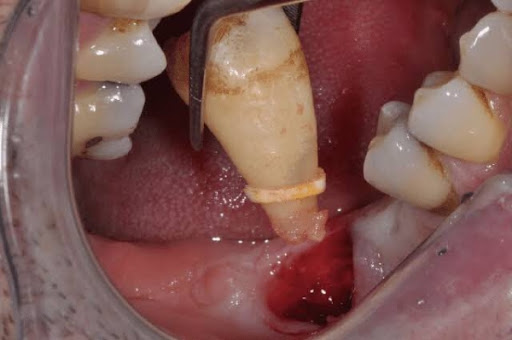

Hình ảnh sau khi nhổ răng khôn

Dưới đây là một số hình ảnh lỗ sau khi nhổ răng khôn của bạn tại Nha Khoa Miền Tây: